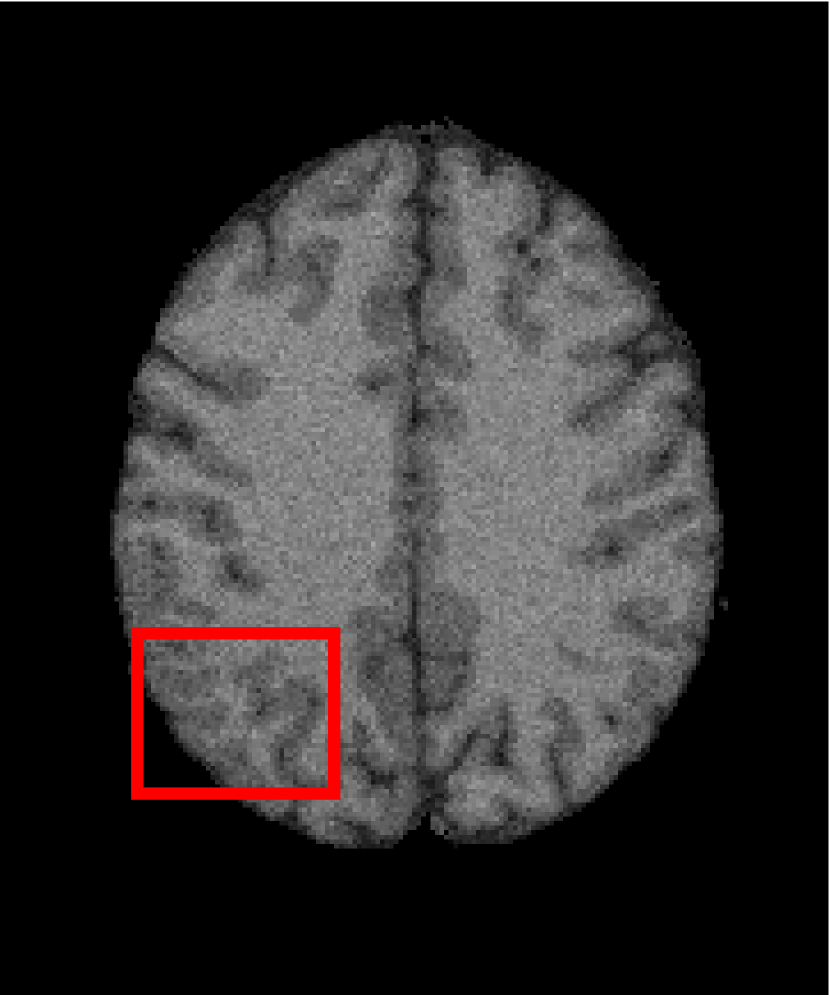

In the second experiments, we segment two medical images coming from a simulated brain database (BrianWeb): http://www.bic.mni.mcgill.ca/brainweb/. The two images are generated by T1 modality with slice thickness of 1mm resolution, 9% noise and 20% intensity non-uniformity. Here, the two images are represented two slices in the axial plane with the sequence of 100 and 110. Moreover, there are golden standard segmentations in the dataset. We set the numbers of clusters to 4. The visual comparisons are illustrated in Figs. 6 and 7.

By focusing on the marked red square in Figs. 6 and 7, we easily find that FCM_S1, FCM_S2, FGFCM and ARKFCM are sensitive to noise. FLICM and KWFLICM are vulnerable to severe intensity inhomogeneity. FRFCM brings overly smooth results due to the use of gray level histograms. WFCM and DSFCM_N cause several contours to change. However, LRFCM acquires clear contours and suppresses noise adequately. Moreover, we find that the segmentation result of LRFCM is closer to ground truth.